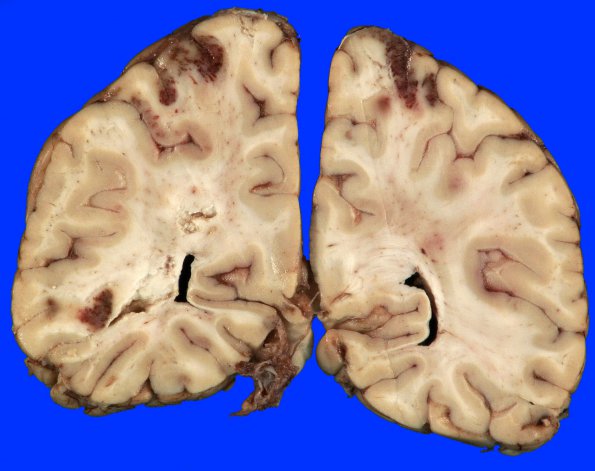

8B3 Infarcts, watershed with uncal herniation (Case 8) Gross _1

8B3,4 Hemorrhagic infarcts involving the cerebral artery watersheds.